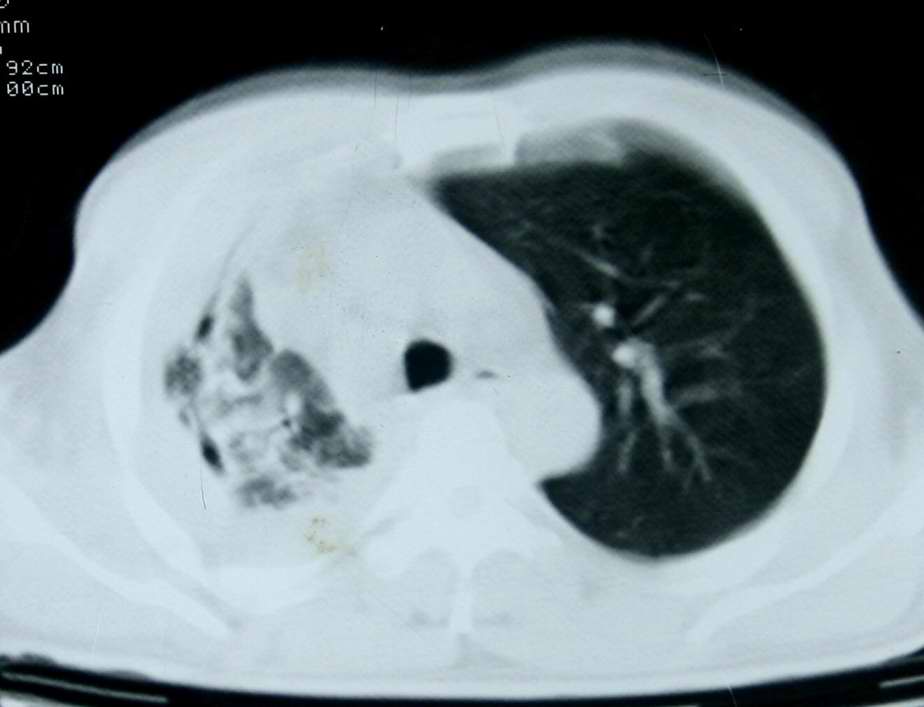

患者,男 ,48岁,反复咯血三个月,每三到五天咯一次,每次约200ml,鲜红色,无明显咳痰,咳嗽明显,无明显胸痛,无发烧,初期以抗感染、止血治疗,第一次ct报占位,支气管镜未见明显ca细,肺ca标志物、tb抗体均阴性,经过垂体后叶素、酚妥拉明、头胞他定、洛美沙星、立止血等治疗后,现病人一般情况好,停止咯血10天,咳嗽减少,咳黄脓痰,每日一次,每次30ml。现复查ct

右肺膨胀不全,纵隔右侧移位。肺内有感染,胸腔有积液。建议老片对比。

1)考虑右肺继发性肺结核合并感染。2)右侧胸腔积液+胸膜增厚。

感染性病变,结核可能性大,伴结核性胸膜炎。